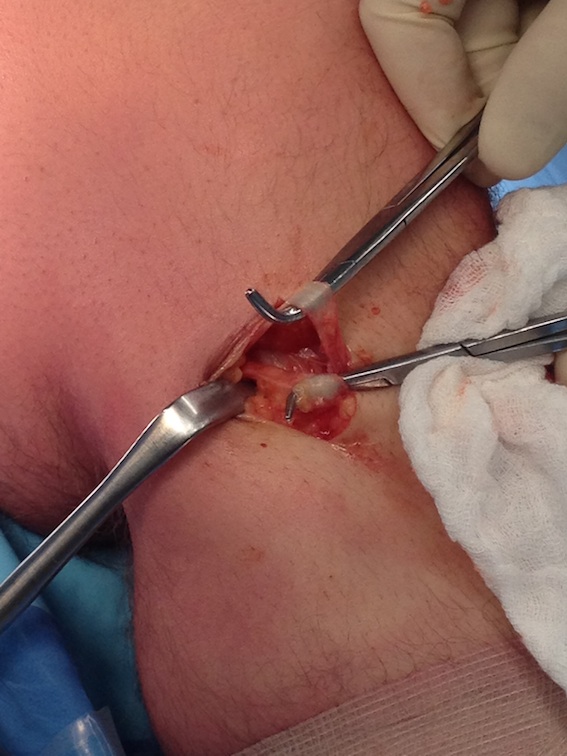

If blow out cortex, can also use extended endobutton

- wider than 10 mm

- often when this is pulled through, will go too far and lodge in vastus lateralis

- in which case cut down to endobutton and seat securely on femur

Uncertain if endobutton has flipped

- check with II

- cut down on lateral femoral cortex

- supplement with interference screw